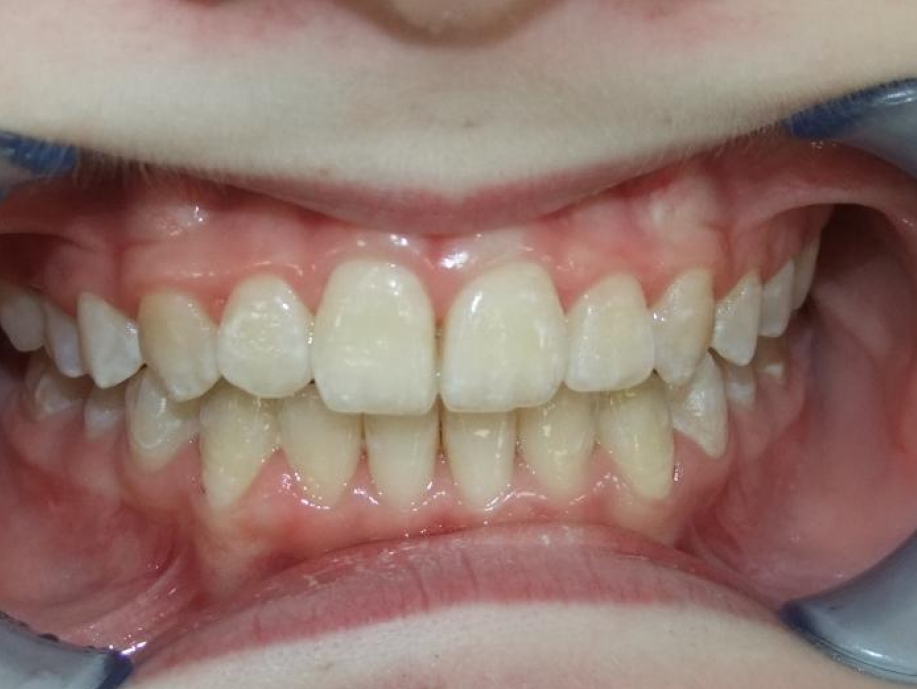

eindfoto